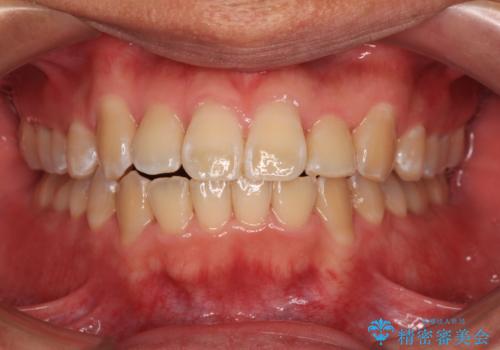

- 八重歯と上下前歯のでこぼこを気にして来院された患者様です。

上下前歯部叢生のスペース獲得のため、上下顎左右小臼歯各1歯(計4本)と全ての親知らずを抜歯して、矯正治療を行うこととしました。

上下の正中位置が大きくずれていたため、治療期間の長期化や正中が合わないまま終了することが予想されましたが、思っていた以上にスムーズに歯が移動し、満足いただける仕上がりとなりました。